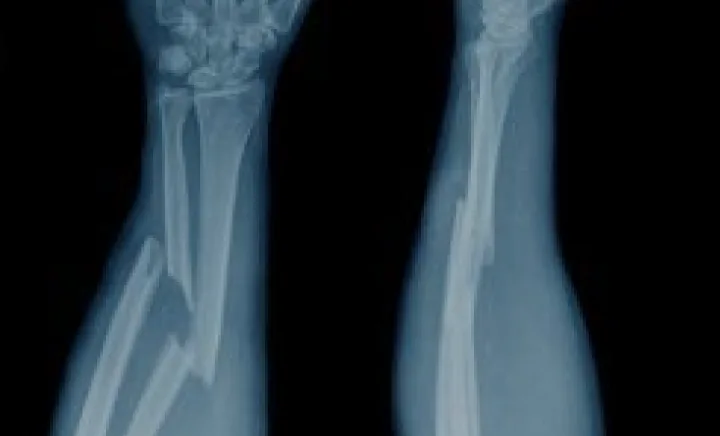

Bone fractures involve disruption of bone structure that may influence mobility, stability, and overall functional recovery. The healing process typically requires structured orthopedic care, rest, and gradual rehabilitation. In regenerative medicine, supportive therapies such as mesenchymal stem cells (MSCs) and Platelet-Rich Plasma (PRP) are increasingly explored as complementary approaches aimed at assisting cellular signaling pathways, inflammation regulation, and tissue-support environments under medical supervision.

Bone recovery occurs in several biological phases, including inflammation control, soft callus formation, hard callus development, and gradual remodeling. Each phase involves complex cellular communication and tissue-repair mechanisms. Factors such as age, nutrition, injury severity, and overall health status can influence recovery timelines and structural stability.